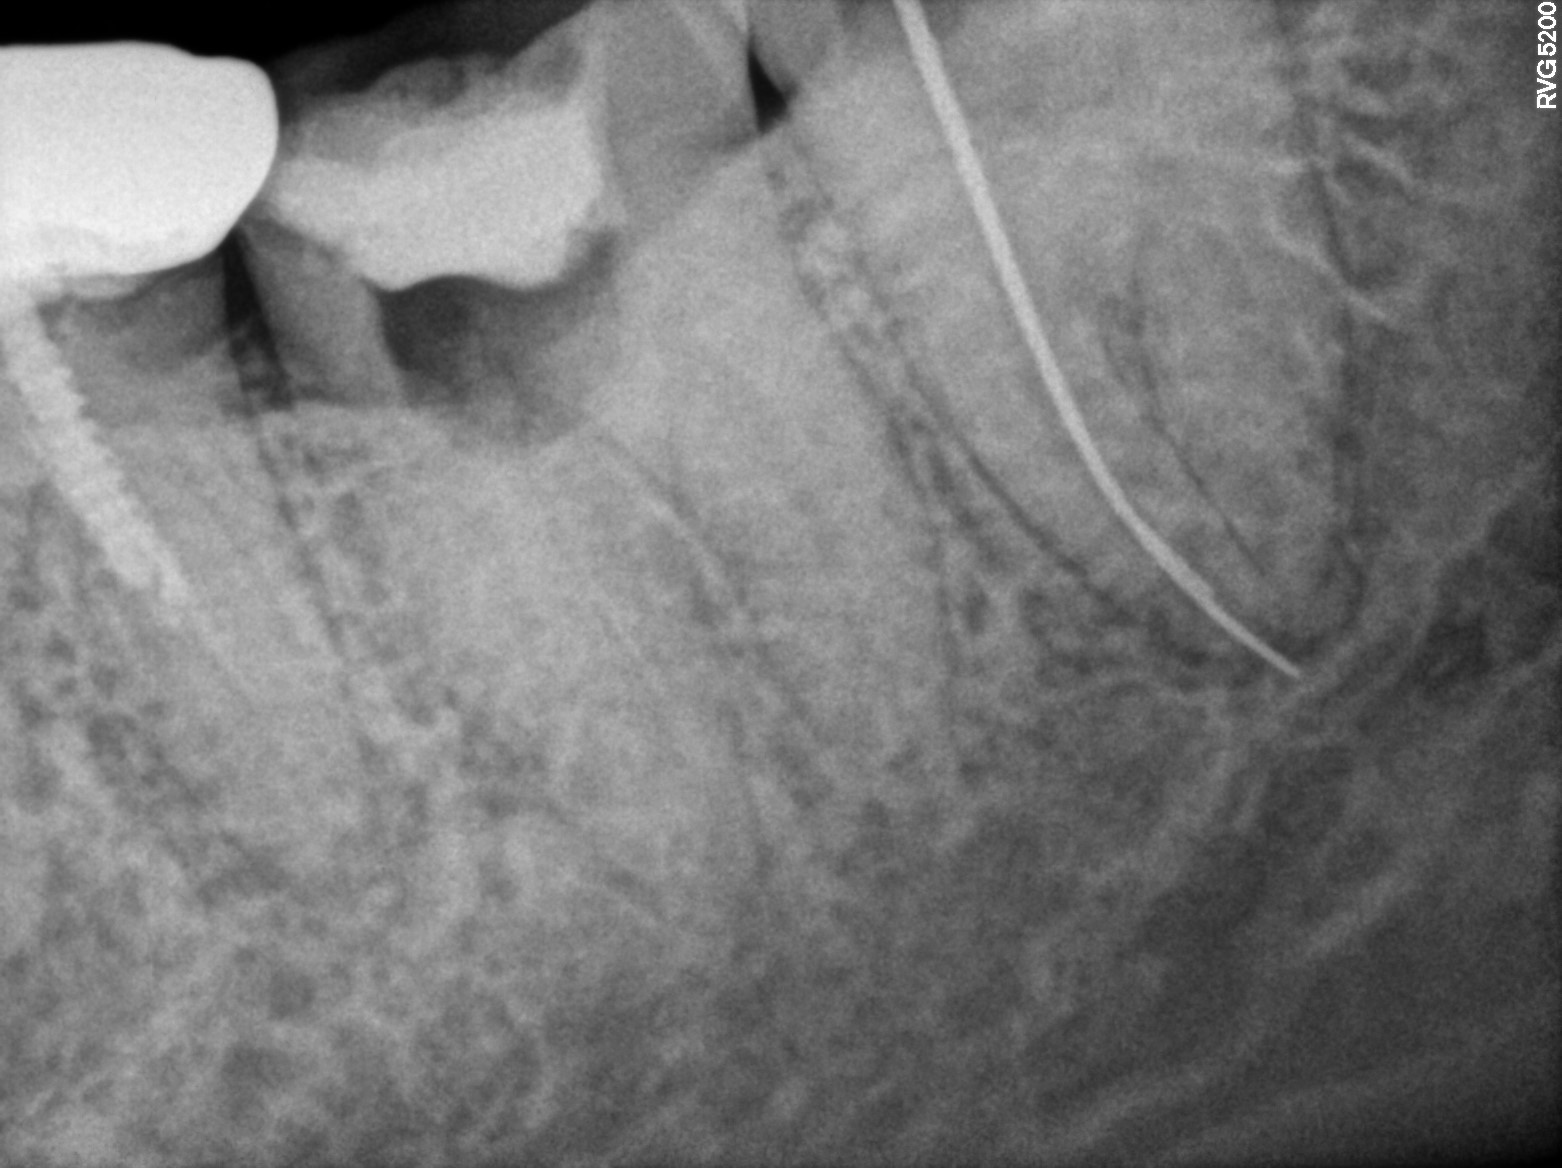

Dental Radiographs FHIR: DocumentReference · LOINC 24641-7

R58.jpg

24641-7